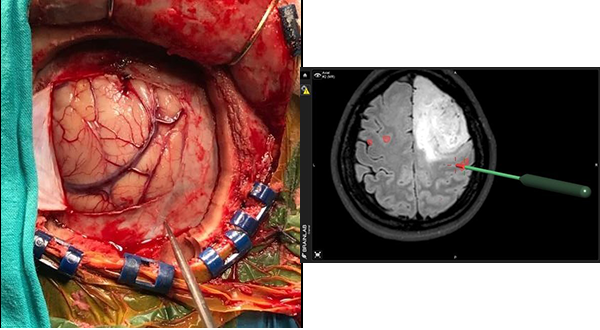

La cirugía se inicia, realizando en la estación de trabajo del navegador Brain Lab Vector Vision II la fusión de imágenes pre quirúrgicas establecidas en el protocolo de neuronavegación antes mencionado por un procedimiento de fusión automática. La secuencia funcional BOLD se fusiona de manera manual, ajustando el tiempo que duran las tareas motoras y los períodos de descanso.

Una vez anestesiado el paciente y fijo a un clamp de Mayfield se realiza el co registro de las imágenes pre quirúrgicas con el paciente a través de registros indirectos de fusión de superficie (Surface Matched) por registro infrarojo, ó por registro directo de imágenes con tomografía computada intraoperatoria (RDII). Esta forma de registro directo elimina los errores de registro indirecto por sistema infrarrojo o electromagnético. Pero su máxima utilidad es permitir la fusión de las imágenes cualquiera fuese la posición quirúrgica de la cabeza ya que la TC intraoperatoria hace visible todo el volumen del cráneo para su correcta fusión con el resto de las imágenes pre quirúrgicas.

Con ayuda de la herramienta de corte se planifica una craneotomía ajustada al criterio de abordaje mínimamente invasivo que exponga los límites del tumor y el área funcional motora indicada por la RMf.

- Monitoreo Neurofisiológico Intraoperatprio

Realizado el colgajo dural el primer paso es la identificación del surco central por sus características morfológicas en la secuencia T1 de la RMN. Luego se procede a corroborar la funcionalidad cortical pre y post central de la corteza anatómica observada en la RMN, con ayuda de un electrodo de cuatro polos para verificar la inversión de fase de la onda de respuesta N20 en un registro de Potencial Evocado Somato-Sensitivo por estimulación eléctrica del nervio mediano contralateral a la lesión, esto permite la localización neurofisiológica del surco central.

3º Colocación de etiquetas numeradas sobre la superficie cortical, y estimulación espacial cortical directa (ECD)

El tercer paso del monitoreo intraoperatorio es la colocación de stickers numerados que nos permitan reconocer la relación espacial de la corteza quirúrgica con al área de activación de la RMfm. De esta manera se colocaron sobre la superficie cortical distribuyendo en forma aleatoria etiquetas estériles numeradas de 0.5 x 0.5 cm. separadas por una distancia aproximada de 1 cm. Las etiquetas cubrieron toda el área de la craneotomía incluyendo la corteza del tejido funcional registrado en la RMfm (expuesto en el abordaje) y la superficie cortical del tumor. Luego se procedió a la estimulación cortical directa (ECD) con estimulación bipolar con una corriente inicial de 4 mAmp, y si no se obtenían respuestas se incrementó sucesivamente a 8 y 12 mAmp. una frecuencia de 60 Hz y tres pulsos de 0.2 mseg de duración.